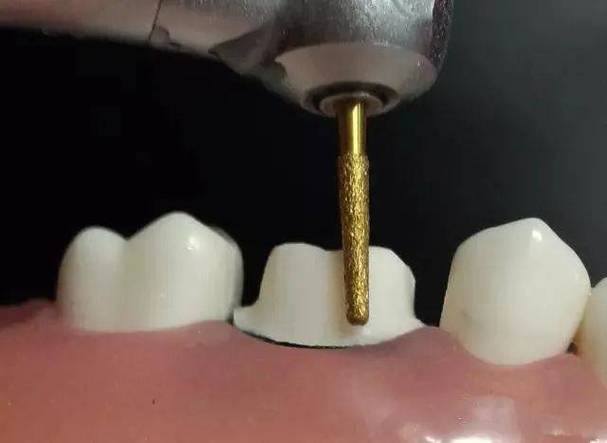

- 预备工具:直角肩台预备车针(如896号、TR-13号)或火焰形车针。

- 先用圆头车针去除牙体倒凹,确定共同就位道;

- 沿牙颈部牙龈缘下方1.0mm处,用车针垂直于牙体长轴磨出1.0-1.5mm深的沟槽,内线角圆钝,避免尖锐转折;

- 修整沟槽底部,确保宽度均匀,无肩台中断或台阶。